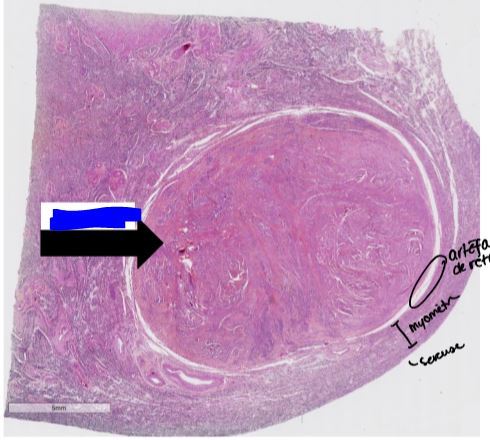

léiomyome utérin

tumeur bénigne très ronde

1. on ne voit pas d’atypie des cellules et absence de mitose

2. cellules musculaires lisses coupées dans tous les sens avec faisceau de collagène associé